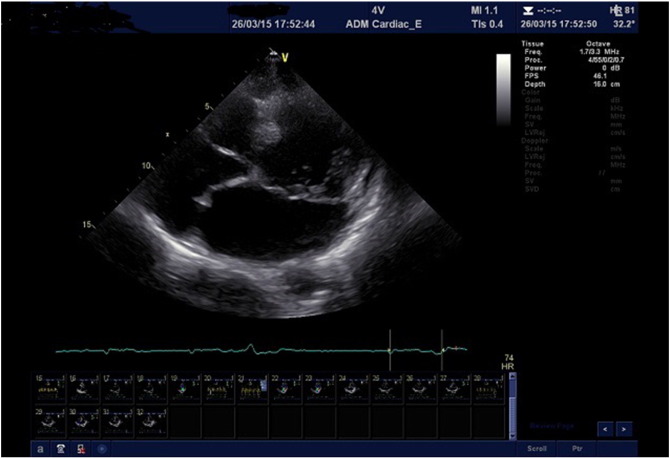

This case demonstrates an important, although unusual, caveat in clinical cardiology. The simultaneous presence of an interatrial septal aneurysm created the erroneous impression of severe left atrial enlargement. The dotted line in Fig. 2 indicates the actual position of the interatrial septum if one needs to measure the transverse diameter.

The dotted line indicates the actual position of the interatrial septum when one ...

Fig. 2.

The dotted line indicates the actual position of the interatrial septum when one needs to measure the transverse diameter of the left atrium.